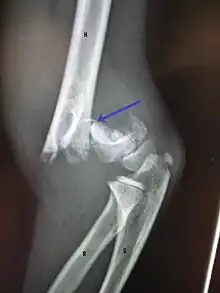

A displaced supracondylar fracture in a child

Distal humerus fractures usually occur as a result of physical trauma to the elbow region. If the elbow is bent during the trauma, then the olecranon is driven upward, producing a T- or Y-shaped fracture or displacing one of the condyles.[7]